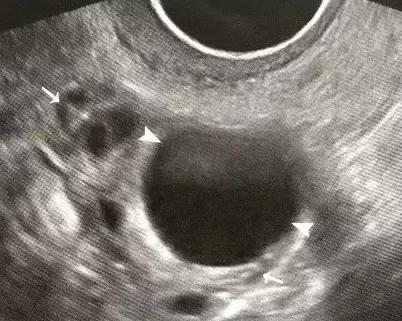

卵泡监测在备孕的时候作用还是很大的,卵泡监测能看出卵泡的发育状态以及是否已经排卵。这在备孕之中可以方便女性在排卵之后安排同房的时间来提高受孕的几率。也可以在备孕中检查出女性是否患有排卵类的疾病从而对受孕产生了影响。在早期发现了病及时治疗的话对女性的生育影响就很小了,所以卵泡监测在备孕中还是比较重要的。